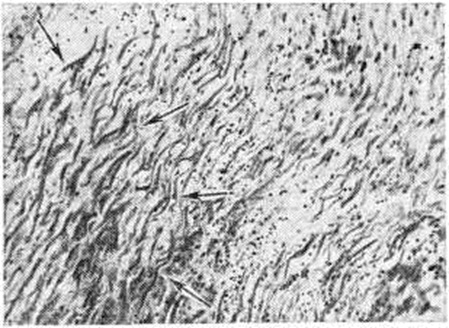

Наиболее часто инфаркт миокарда развивается в передней стенке левого желудочка (рисунок 1), то есть в бассейне кровоснабжения передней межжелудочковой артерии. Второе место по частоте занимают Инфаркт миокарда задней стенки левого желудочка. Некротические изменения, по данным А. В. Смольянникова, в межжелудочковой перегородке отмечаются в 10—20% различных вариантов локализации Инфаркт миокарда, на боковую стенку он распространяется в 5—6% случаев, на сосочковые мышцы — в 25% случаев Субэндокардиальный Инфаркт миокарда чаще всего связан со стенозирующим атеросклерозом, не сопровождающимся окклюзией или тромбозом сосуда. В большинстве случаев субэндокардиальный Инфаркт миокарда располагается в передней или задней папиллярной мышце левого желудочка, задней или передней стенке левого желудочка и в левожелудочковой части межжелудочковой перегородки. Развитие крупноочаговых инфарктов связано, как правило, с окклюзией крупных ветвей коронарных артерий. При нарушении кровотока в верхней трети передней межжелудочковой артерии инфаркт обычно локализуется в области передней стенки, передних 2/3 межжелудочковой перегородки и верхушке сердца, иногда распространяясь на боковую стенку левого желудочка. Инфаркт задней стенки более полиморфен в отношении локализации и размеров, что обусловлено типом кровоснабжения сердца. В зависимости от особенностей васкуляризации задней стенки и межжелудочковой перегородки различают правый, левый, а также средние типы кровоснабжения сердца с их вариантами (средне правый и средне левый). При левом типе эти отделы снабжаются кровью из левой венечной артерии, при правом типе — из правой, при среднем типе задняя стенка левого желудочка получает кровь из левой венечной артерии, а задняя стенка правого желудочка и задний отдел межжелудочковой перегородки — из правой венечной артерии. При средне левом типе задняя стенка левого желудочка и частично задний отдел перегородки получают кровь из левой венечной артерии, а правая венечная артерия, снабжая заднюю стенку правого желудочка, принимает участие также в кровоснабжении заднего отдела перегородки, которая, следовательно, имеет два источника кровоснабжения. При средне-правом типе, встречающемся наиболее часто (около 50% случаев), медиальная часть задней стенки левого желудочка и межжелудочковая перегородка получают кровь из правой венечной артерии, а левая венечная артерия снабжает кровью лишь латеральную часть задней стенки левого желудочка. При правом и левом типах кровоснабжения возможности развития коллатералей меньше, чем при средних типах. Возникновение Инфаркт миокарда в задней стенке левого желудочка связано при среднем и левом типах кровоснабжения с поражением левой венечной артерии, при правом и средне-правом типах — с поражением правой венечной артерии. При правом типе кровоснабжения сердца инфаркт захватывает всю заднюю стенку, при средне-правом лишь её медиальную часть. Тромбоз основного ствола левой венечной артерии при левом или средне-левом типах кровоснабжения сердца приводит к возникновению циркулярного Инфаркт миокарда, захватывающего все стенки левого желудочка, межжелудочковую перегородку, а частично и заднюю стенку правого желудочка. У больных Инфаркт миокарда на фоне хронический ишемической болезни сердца (смотри полный свод знаний) нередко макроскопически обнаруживают крупные рубцы, мелкоочаговый кардиосклероз (смотри полный свод знаний), преимущественно в субэндокардиальных отделах левого желудочка сердца. Рубцы закономерно образуются при повторных Инфаркт миокарда, но обнаруживаются и при отсутствии в анамнезе клинический, проявлений Инфаркт миокарда. В зоне рубцов пристеночный эндокард бывает утолщен за счёт новообразованных коллагеновых и эластических волокон (вторичный фиброэластоз эндокарда). Свежие некрозы часто локализуются в зоне, прилегающей к рубцам. В большинстве случаев вес сердца увеличен до 400 грамм и выше даже при отсутствии гипертонической болезни. Особенно увеличен вес сердца при наличии рубцов Гипертрофия сердца может быть тотальной или касаться преимущественно левого, а иногда правого желудочка сердца. Последнее наблюдается при аневризмах левого желудочка сердца, осложняющихся гипертензией малого круга кровообращения в связи с хронический левожелудочковой недостаточностью. Микроскопически изменения в сердце при Инфаркт миокарда выявляются в первые часы его развития. При светооптическом исследовании, если смерть наступила в первые 2 часа от начала клинический, проявлений Инфаркт миокарда, обнаруживаются лишь очаговые изменения в стенках магистральных стволов венечных артерий — набухание интимы, белковое пропитывание субэндотелиальных отделов, фиброзной ткани бляшек, содержимого атером; отмечаются свышеежие кровоизлияния в поверхностные отделы бляшек, вокруг новообразованных сосудов, в адвентиции, а также в новообразованных сосудах, питающих бляшки. Эти изменения отражают острые нарушения проницаемости сосудистых мембран в связи с прогрессирующей гипоксией. В миокарде выявляются полнокровие сосудов, стазы в капиллярах, выраженный отёк стромы, набухание стенок мелких интрамуральных и субэндокардиальных артерий. Через 2—3 часа от начала болезни определяются первоначальные изменения в мышечных волокнах в виде неравномерной их окраски с образованием грубых поперечных полос, глыбок, наплывов («мышечные контрактуры» — рисунок 2). Через 4—5 часов в субэндокардиальных отделах сердца появляются фокусы фуксинофильной дегенерации, характеризующиеся набуханием мышечных клеток, их интенсивной окраской кислыми красками и метахромазией при окраске по Селье. Эти изменения связаны с плазматическим пропитыванием погибающих мышечных клеток Электронно-микроскопическое исследование, применяемое главным образом в экспериментальных исследованиях (лигирование коронарной артерии), выявляет изменения в сердечной мышце уже через 15—20 минут Первоначальные изменения обнаруживаются в митохондриях, которые набухают, матрикс их просветляется, кристы набухают и распадаются и митохондрии приобретают вид пузырьков. Эти изменения вначале появляются в митохондриях, расположенных под сарколеммой, а затем и в локализующихся между миофибриллами. Просвет цистерн эндоплазматического ретикулума увеличивается. Диски и поперечные полосы мышечных клеток не контурируются, исчезают гранулы гликогена. В ядре особых изменений не наблюдается. При контрастировании срезов в растворе уксуснокислого свинца отмечается неравномерная активность АТФ-азы: наибольшее количество осаждённого свинца располагается на наружных оболочках митохондрий, в набухших кристах его значительно меньше, в миофибриллах активность фермента почти полностью отсутствует.

При ишемии в течение 6—8 часов отёк мышечного волокна достигает высшей степени. Часть митохондрий теряет оболочку и частично или полностью растворяется, сливается друг с другом. Некоторые митохондрии резко набухают, деформируются. В эндоплазматическом ретикулуме выявляются крупные вакуоли. Миофибриллы находятся в состоянии релаксации, на месте разрушенных миофибрилл располагаются многочисленные жировые капли. Активность окислительно-восстановительных ферментов падает. Через 7—8 часов от начала ишемии можно видеть полное разрушение митохондрий. Эндоплазматический ретикулум вакуолизирован, мембраны его разрушены. Активность окислительно-восстановительных ферментов отсутствует. Возникают деструктивные изменения в ядре: оно плохо контурируется, становится гомогенным, разрушается оболочка ядра, хроматин приобретает крупноглыбчатую форму и скапливается у ядерной оболочки. При люминесцентной микроскопии через 1 — 2 часа после лигирования коронарной артерии, а также в случаях внезапной смерти выявляется изменение окраски мышечных волокон, которые начинают светиться зелёным светом. Это обусловлено накоплением в ткани кислых продуктов обмена. Через 4—6 часов при обработке срезов 3,4-бензпиреном видны многочисленные мелкие жировые капельки, не выявляемые при окраске Суданом III — IV, Суданом черным и другими методами. При гистохимический исследовании самым ранним признаком локальной ишемии является резкое уменьшение содержания гликогена в мышечных волокнах, что отмечается уже через 30 минут после лигирования коронарной артерии, а также при скоропостижной смерти при раннем вскрытии. Через 4—6 часов гликоген в зоне ишемии не определяется, за исключением отдельных пучков, расположенных под эндокардом и вокруг сосудов. Это, а также большая активность дегидрогеназы молочной кислоты указывает на усиление гликолитических процессов. Через 2—4 часа от начала ишемии изменяется активность окислительно-восстановительных ферментов Вначале активность сукцинатдегидрогеназы кратковременно усиливается (нарушается распределение, увеличивается количество гранул формазана и усиливается их окраска), но через 4—6 часов наступает её угнетение (уменьшается количество и ослабляется окраска зёрен формазана). Полностью активность ферментов исчезает через 12 часов от начала опыта. В сформированном инфаркте можно видеть три зоны активности ферментов: в очаге некроза — полное отсутствие её (зерна формазана не выявляются), в пограничной зоне — пониженная активность ферментов (уменьшение количества зёрен формазана и ослабление их окраски), в отдалённых участках — нормальная или повышенная активность ферментов Через 6 —10 часов от начала развития Инфаркт миокарда светооптической микроскопией выявляются скопления лейкоцитов в капиллярах поражённого миокарда, миграция лейкоцитов за стенки сосудов; обнаруживаются диапедезные кровоизлияния по периферии формирующегося очага некроза. В последующие часы очертания набухших мышечных волокон становятся неправильными, исчезает их поперечная исчерченность. В течение суток происходит полный некроз мышечных волокон. К концу первых суток количество очагов фуксинофильной дегенерации нарастает, они сливаются между собой, образуя крупные поля, а в строме появляются лейкоцитарные инфильтраты. По периферии формируется демаркационная линия, состоящая из лейкоцитов (рисунок 3), к которым примешиваются гистиоцитарные элементы. Количество лейкоцитов нарастает, и к 48 часам от начала болезни они образуют обильные скопления по периферии инфаркта между мёртвыми и сохранившимися мышечными волокнами. Типичный Инфаркт миокарда характеризуется зональностью строения. По периферии некротического фокуса выявляется зона повреждения кардиомиоцитов, вокруг которой формируется зона ишемии, выявляемая морфологически лишь с помощью посмертной капиллярографии. Зона повреждения выражена неравномерно. Со стороны эндокарда в обычно сохраняющихся волокнах Пуркинье, как и в субэпикардиальных отделах, повреждение выражено незначительно. В краевых отделах, а также в толще очага вокруг сохранившихся периваскулярных островков миокарда повреждение достигает максимальной степени, иногда переходя в некроз.